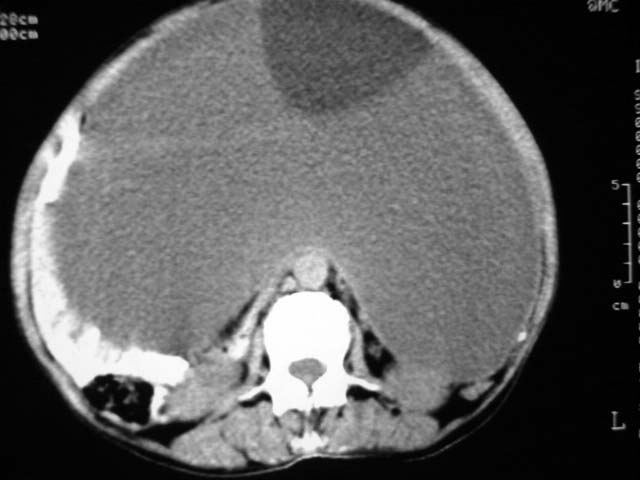

女,75岁,腹部胀大半年余,无其他症状。

考虑来源与卵巢的巨大囊腺瘤或囊肿。

真是腹大如牛,考虑卵巢巨大囊腺瘤或囊肿。

考虑来源于卵巢的巨大囊腺瘤;如果是单纯囊肿不知其前部的更低密度区怎么解释?

考虑来源卵巢巨大黏液性囊腺瘤。